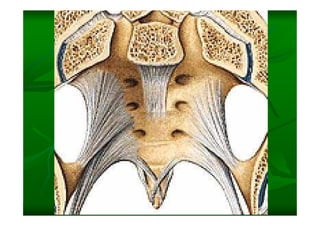

Este documento describe la columna vertebral humana. Está compuesta de 33 vértebras divididas en 7 cervicales, 12 torácicas, 5 lumbares, 5 sacras y 4 cóccigeas. Cada vértebra posee un cuerpo, pedículo, apófisis transversas, apófisis espinosa e inferior y laminas. Las curvaturas de la columna son la lordosis cervical y lumbar y la cifosis torácica y sacra.